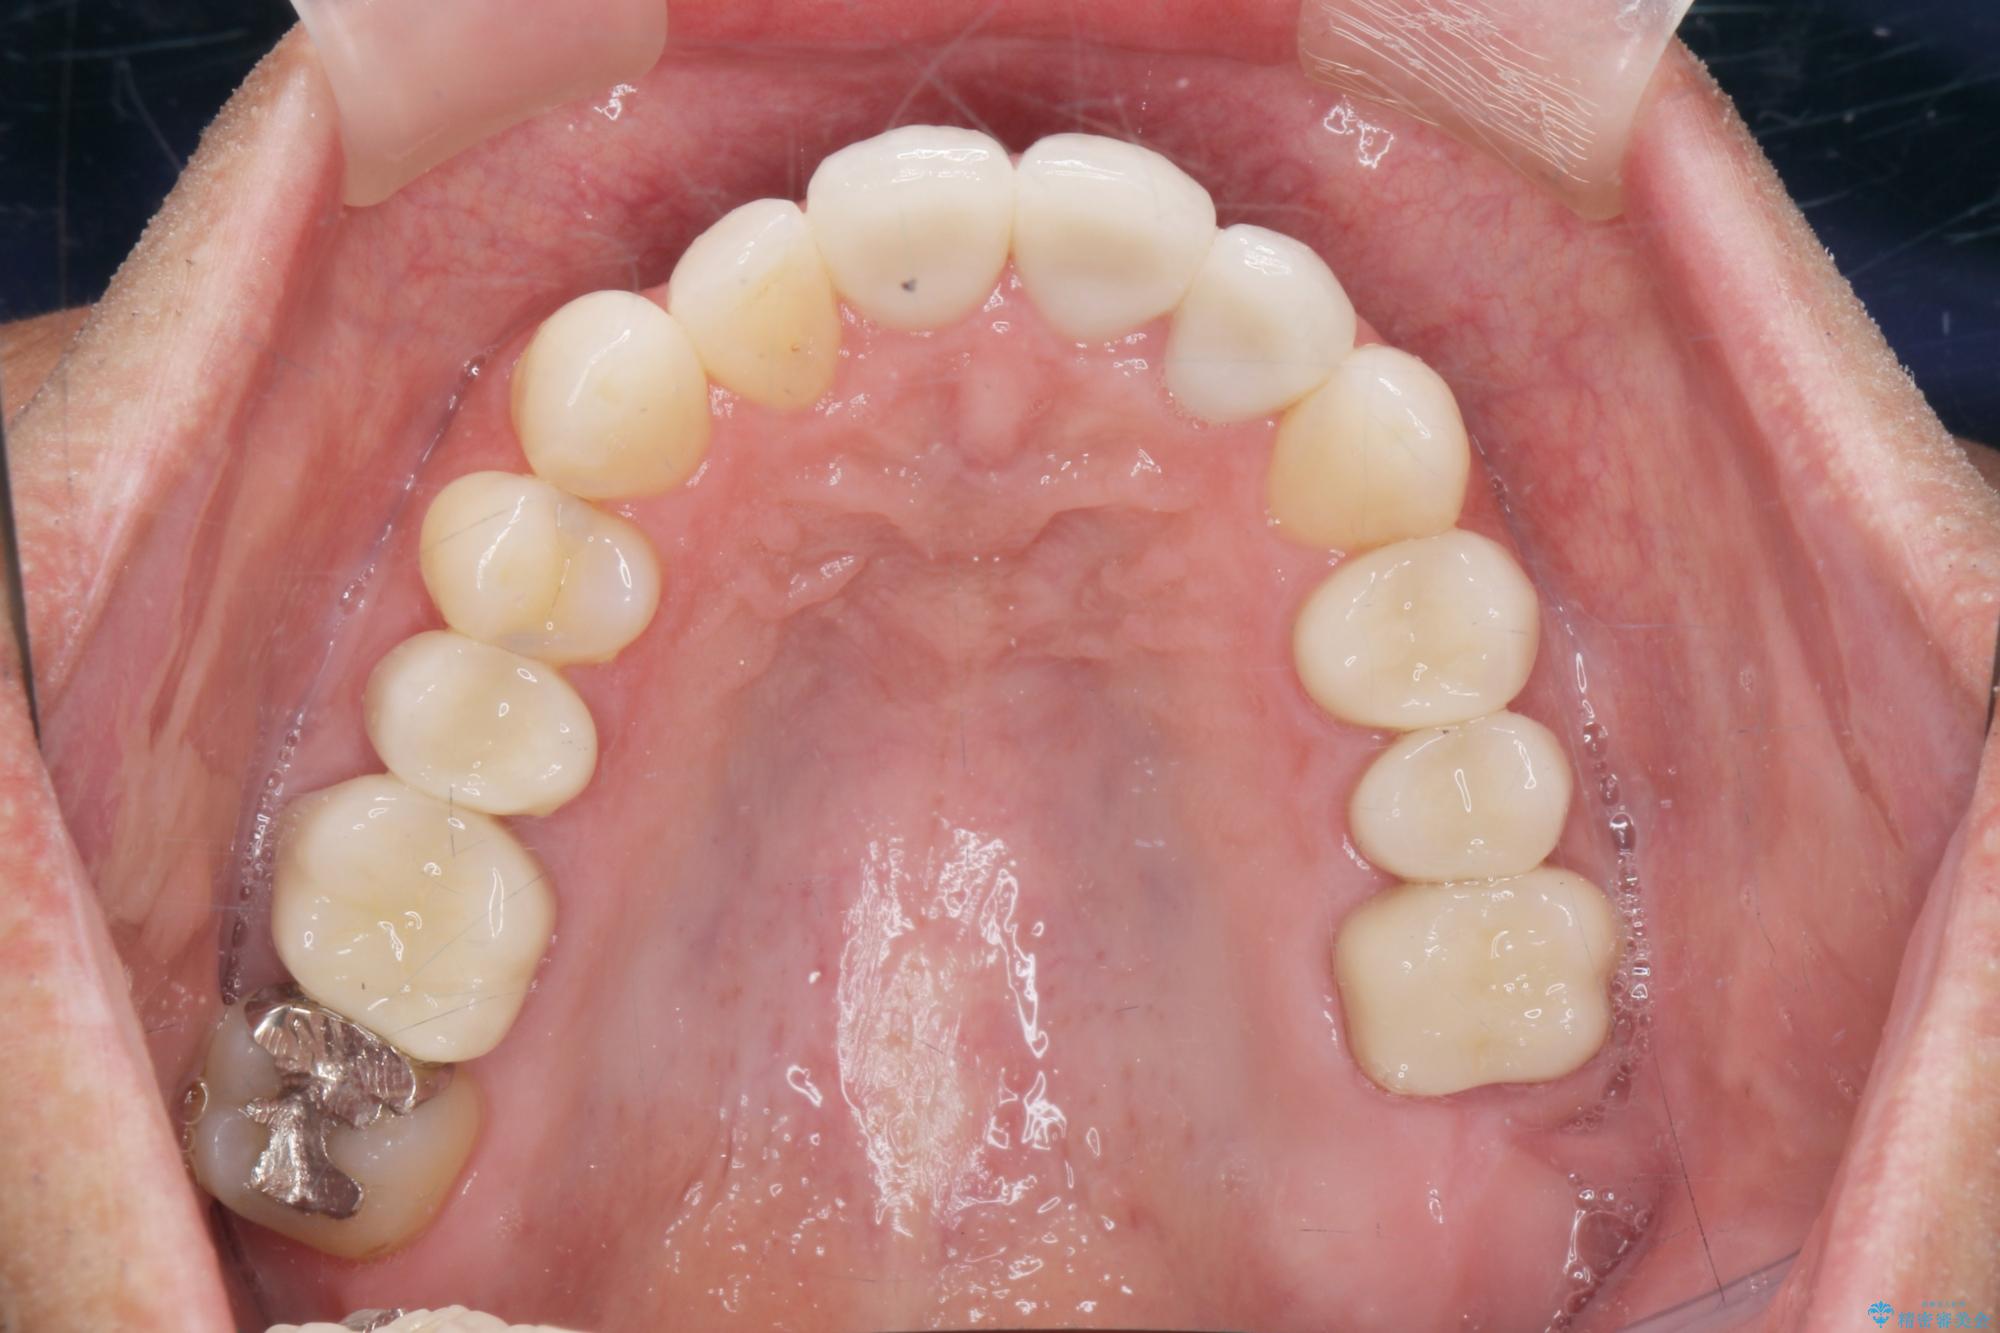

- 突き出た前歯の角度の改善と虫歯治療の改善を求めて来院されました。

虫歯を除去したのち、マウスピース矯正治療を行い、歯並びやがたつきを改善したのち、セラミックに置き換えることで審美性の向上を計画します。

矯正や虫歯治療、セラミック治療といった複合的な治療を一医院で行うことができるのが当法人の大きな特長です。